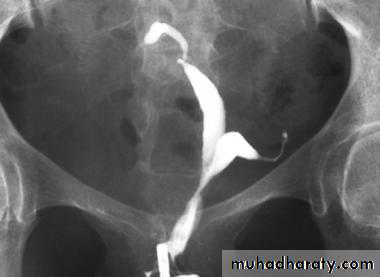

IUCD copper